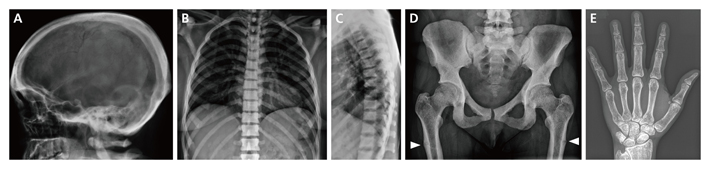

図2 Ikegawa型大理石骨病患者のX線像

X線像により以下A~Eの特徴があることが分かった。

A:頭蓋骨がぶ厚い。B、C:脊椎は一様に骨濃度が高い。D:骨盤と大腿骨の骨濃度が高く、大腿骨の偽骨折(日常のちょっとした動作で骨に亀裂が入ること)が見られる(白矢印)。E: 手の骨の表面を構成する皮質が厚い。